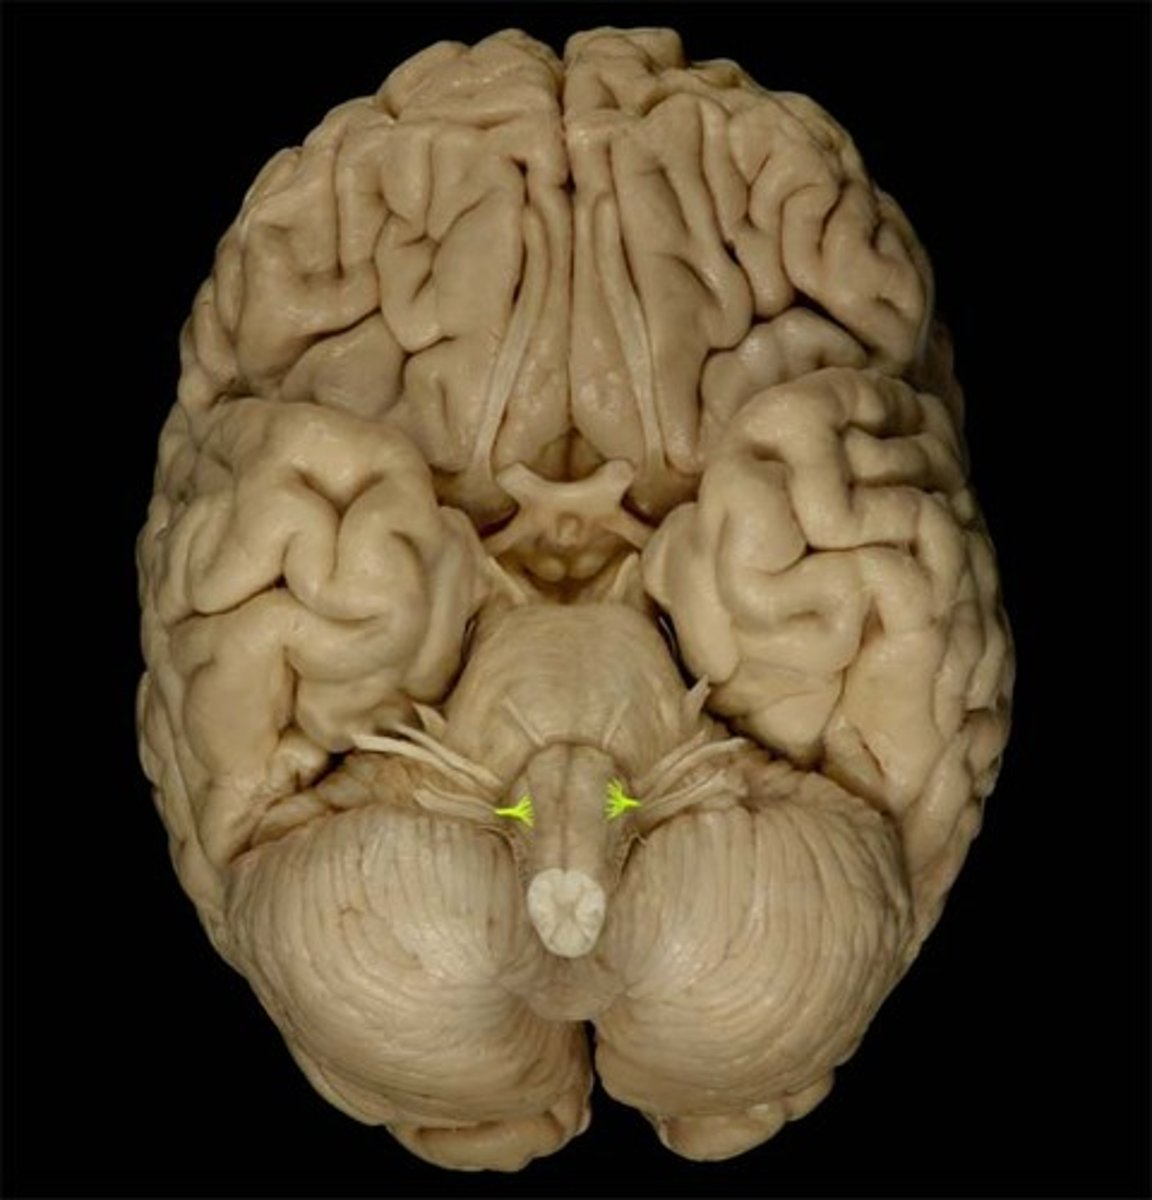

optic nerve (CN II)

Sensory cranial nerve related to vision

optic chiasm

point at which optic nerve fibers cross in the brain

optic tracts

the continuation of the optic nerve fibers beyond the optic chiasma